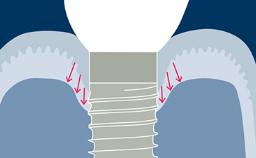

A substituição de dentes perdidos por meio de implantes endósseos tem provado ser uma modalidade de tratamento bem-sucedida para pacientes total e parcialmente desdentados. Este conceito é baseado no fenômeno biológico da osseointegração. Para um bom resultado a longo prazo de uma reconstrução implantossuportada, os tecidos duros e moles precisam ser estáveis e fornecer um suporte adequado para a reconstrução protética. Existem vários fatores de risco que podem afetar as taxas de sucesso e sobrevivência. Um clínico que planeja uma terapia com implantes precisa conhecer os fatores de risco que contribuem para os diferentes tipos de complicações que podem ocorrer após o tratamento.

- identificar os diferentes tipos de complicações que podem estar envolvidas na terapia com implante

- identificar os fatores de risco para essas complicações